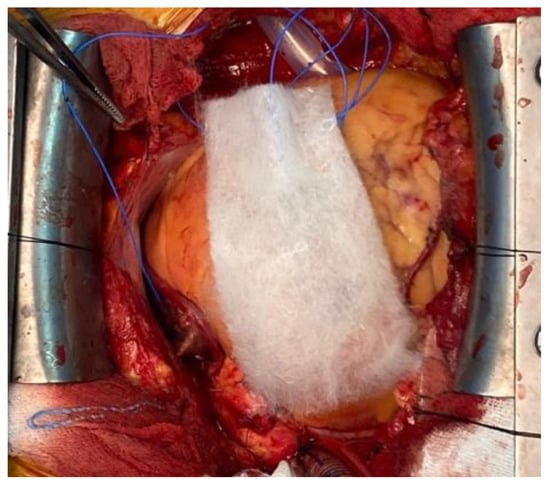

3.2.2. Fibrin Sealants and Fibrin Patches

4.2. Collagen Loaded with Gelatin Microspheres as a New Composite Biomaterial for Haemostatics